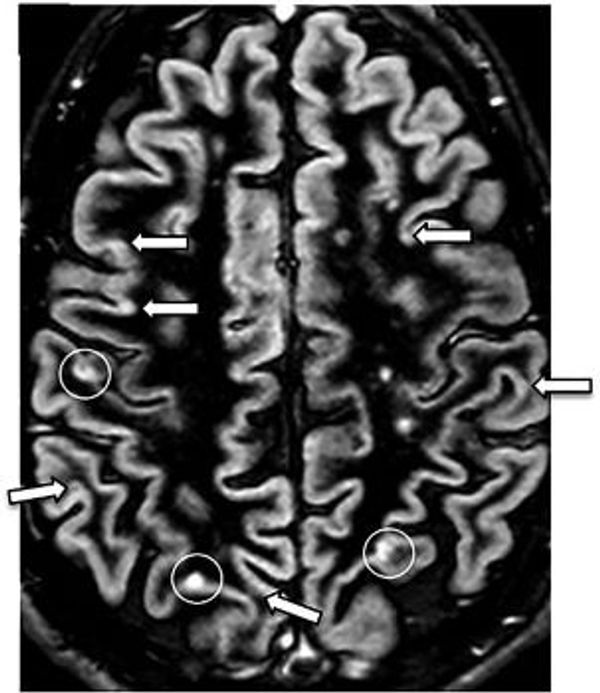

Bij Multiple sclerose wordt deze myelinelaag aangetast. Dit gebeurt door het eigen afweersysteem dat de zenuwcellen aanvalt. MS wordt daarom ook een auto-immuunziekte genoemd. In de myelinelaag ontstaan gaten wat demyelinisatie wordt genoemd. Hierdoor wordt de overdracht van signalen bemoeilijkt en uiteindelijk soms zelfs helemaal niet meer mogelijk. Het lichaam vult de ontstane gaten op met bindweefsel (het kan geen nieuw myeline meer aanmaken), waardoor er littekens ontstaan die niet meer isoleren. Dit littekenweefsel is hard en daaraan dankt de ziekte haar naam: Multiple sclerose betekent letterlijk meerdere verhardingen.